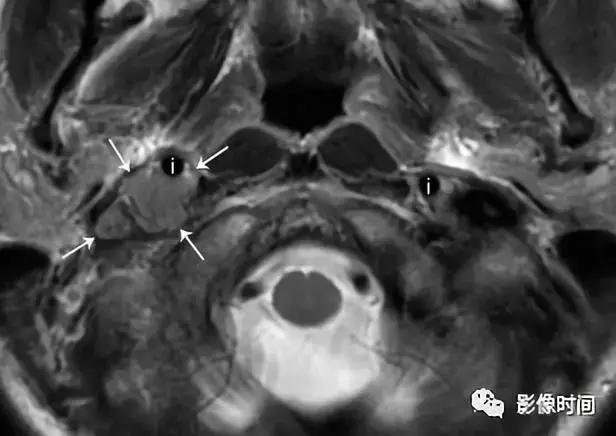

(1).颈动脉体瘤:约占颈部副节瘤的 60%,45-60 岁多见,无明显性别差异。多位于颈总动脉分叉处内侧,往往生长缓慢和无痛,由于病灶靠近 10-12 颅神经,因此患者可以出现吞咽困难、声音嘶哑等。

模式图显示颈动脉体瘤富含血管,并导致颈内动脉及颈外动脉距离增宽,包绕颅神经。增强 CT 显示右侧动脉间隙中心的边界清晰肿块,导致颈内动脉 (i) 和颈外动脉 (e) 分离。颈内静脉向外后移位(j)。左颈动脉间隙 (虚线圆) 显示颈动脉与颈内静脉的正常关系。T2WI 显示边界清晰的信号肿块 (白色箭头),多个内部流动信号 (黑色箭头)。DSA 显示颈动脉分叉处有富血管团块 (箭头)。